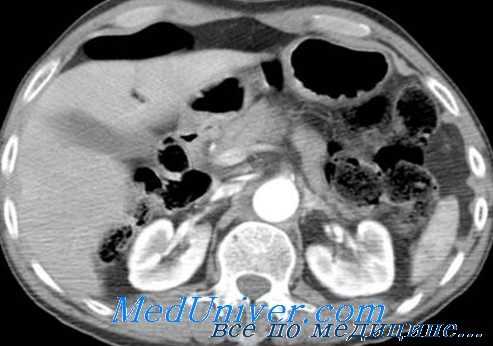

Наиболее распространенным показанием к лапаротомии у этих пациентов, особенно с тяжелой ЧМТ, является свободная жидкость, выявленная при КТ без повреждения паренхиматозного органа. Другим диагностическим выбором у этих пациентов, кроме лапаротомии, может быть ДЛБП, чтобы определить количество лейкоцитов и ферментов.

Пациенты с колотыми ранами оцениваются на основании местоположения повреждения; те, у которых есть раны на боку или спине, подвергаются тройному контрастному КТ, а тем, у которых есть колотые раны на передней брюшной стенке, выполняется хирургическая ревизия раны и ДЛБП. Важно, что ревизия раны — не просто пальцевое обследование, иногда наблюдаемое в травматологическом отделении.

Ревизия раны выполняется в стерильных условиях под местной анестезией, часто с острым расширением раны, чтобы получить прямое визуальное подтверждение глубины проникновения. При положительном результате ревизии раны с проникновением сквозь передний листок апоневроза прямой мышцы или косой мышцы, мы выполняем ДЛБП. По нашему опыту, диагностическая оценка с помощью ревизии и ДЛПБ приводит к тому, что более трети пациентов выписываются из отделения неотложной помощи без дальнейшего дорогостоящего обследования или пребывания в стационаре.

Еще треть пациентов наблюдается в течение 12-24 часов в нашей палате наблюдения после ДЛБП, чтобы убедиться в отсутствии осложнений. Последней трети выполняется лапаротомия на основании клинической оценки и результатов ДЛБП. Уклон авторов в сторону последовательного обследования и тщательного наблюдения для определения потребности в лапаротомии является предпочтительным подходом их учреждения. Другие учреждения выбирают КТ оценку всех стабильных пациентов с любой колотой раной туловища.